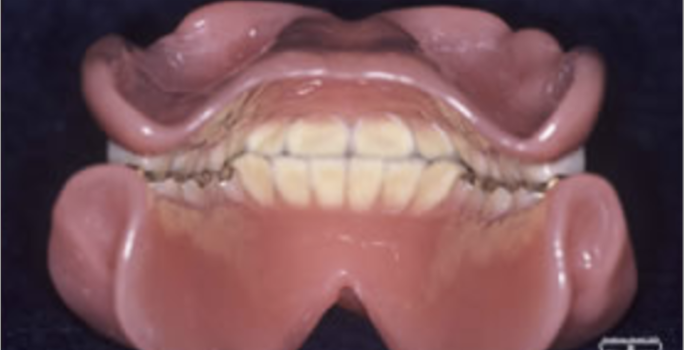

お困りごとを参考に、治療のbefore・afterが確認できます。治療過程や期間、費用などを参考にご覧ください。